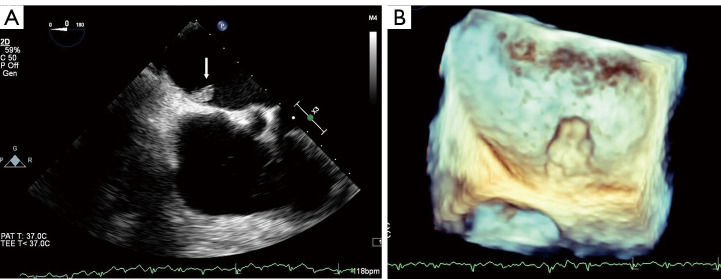

Left atrial myxoma complicated by a coronary artery fistula due to rupture of the feeding artery: a case description.

左房黏液瘤并发供血动脉破裂致冠状动脉瘘1例。